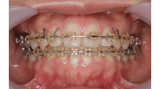

■症例2

Before

After